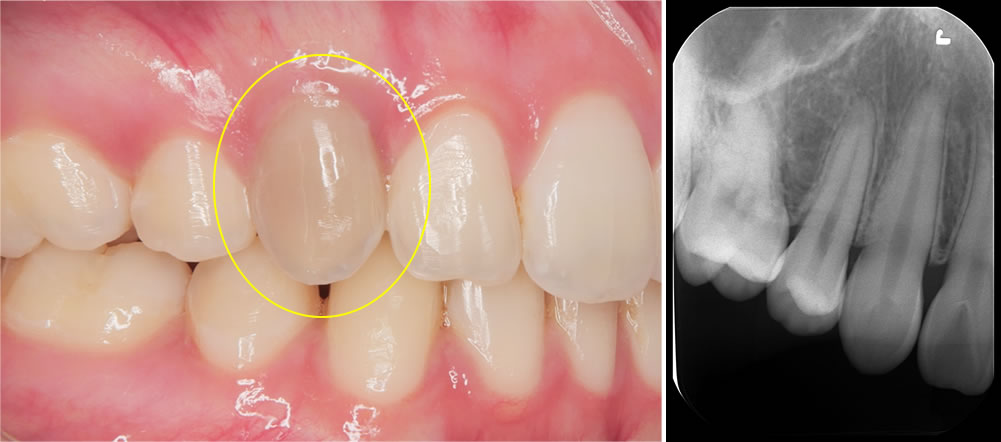

こちらの患者さんは、右上の前歯の色が黒くなってきたことを主訴に来院されました。

写真の通り、この歯だけが変色しており、他院では「削って被せ物にする必要があるかもしれない」と説明を受けていたそうです。

当院ではまず原因を調べるために各種検査を行いました。その結果、右上の前歯は冷たい刺激に反応せず、神経が死んでしまっている(失活歯)と判断しました。

原因として考えられたのは、過去に行われた矯正治療です。歯の根が骨の外に出てしまっており、本来は骨の中に位置すべき歯根が露出していたため、神経がダメージを受けてしまったと考えられます。通常、歯は骨のアーチの中に適切にコントロールして並べることが非常に重要で、それを外れてしまうと神経が死んでしまうリスクが高まります。